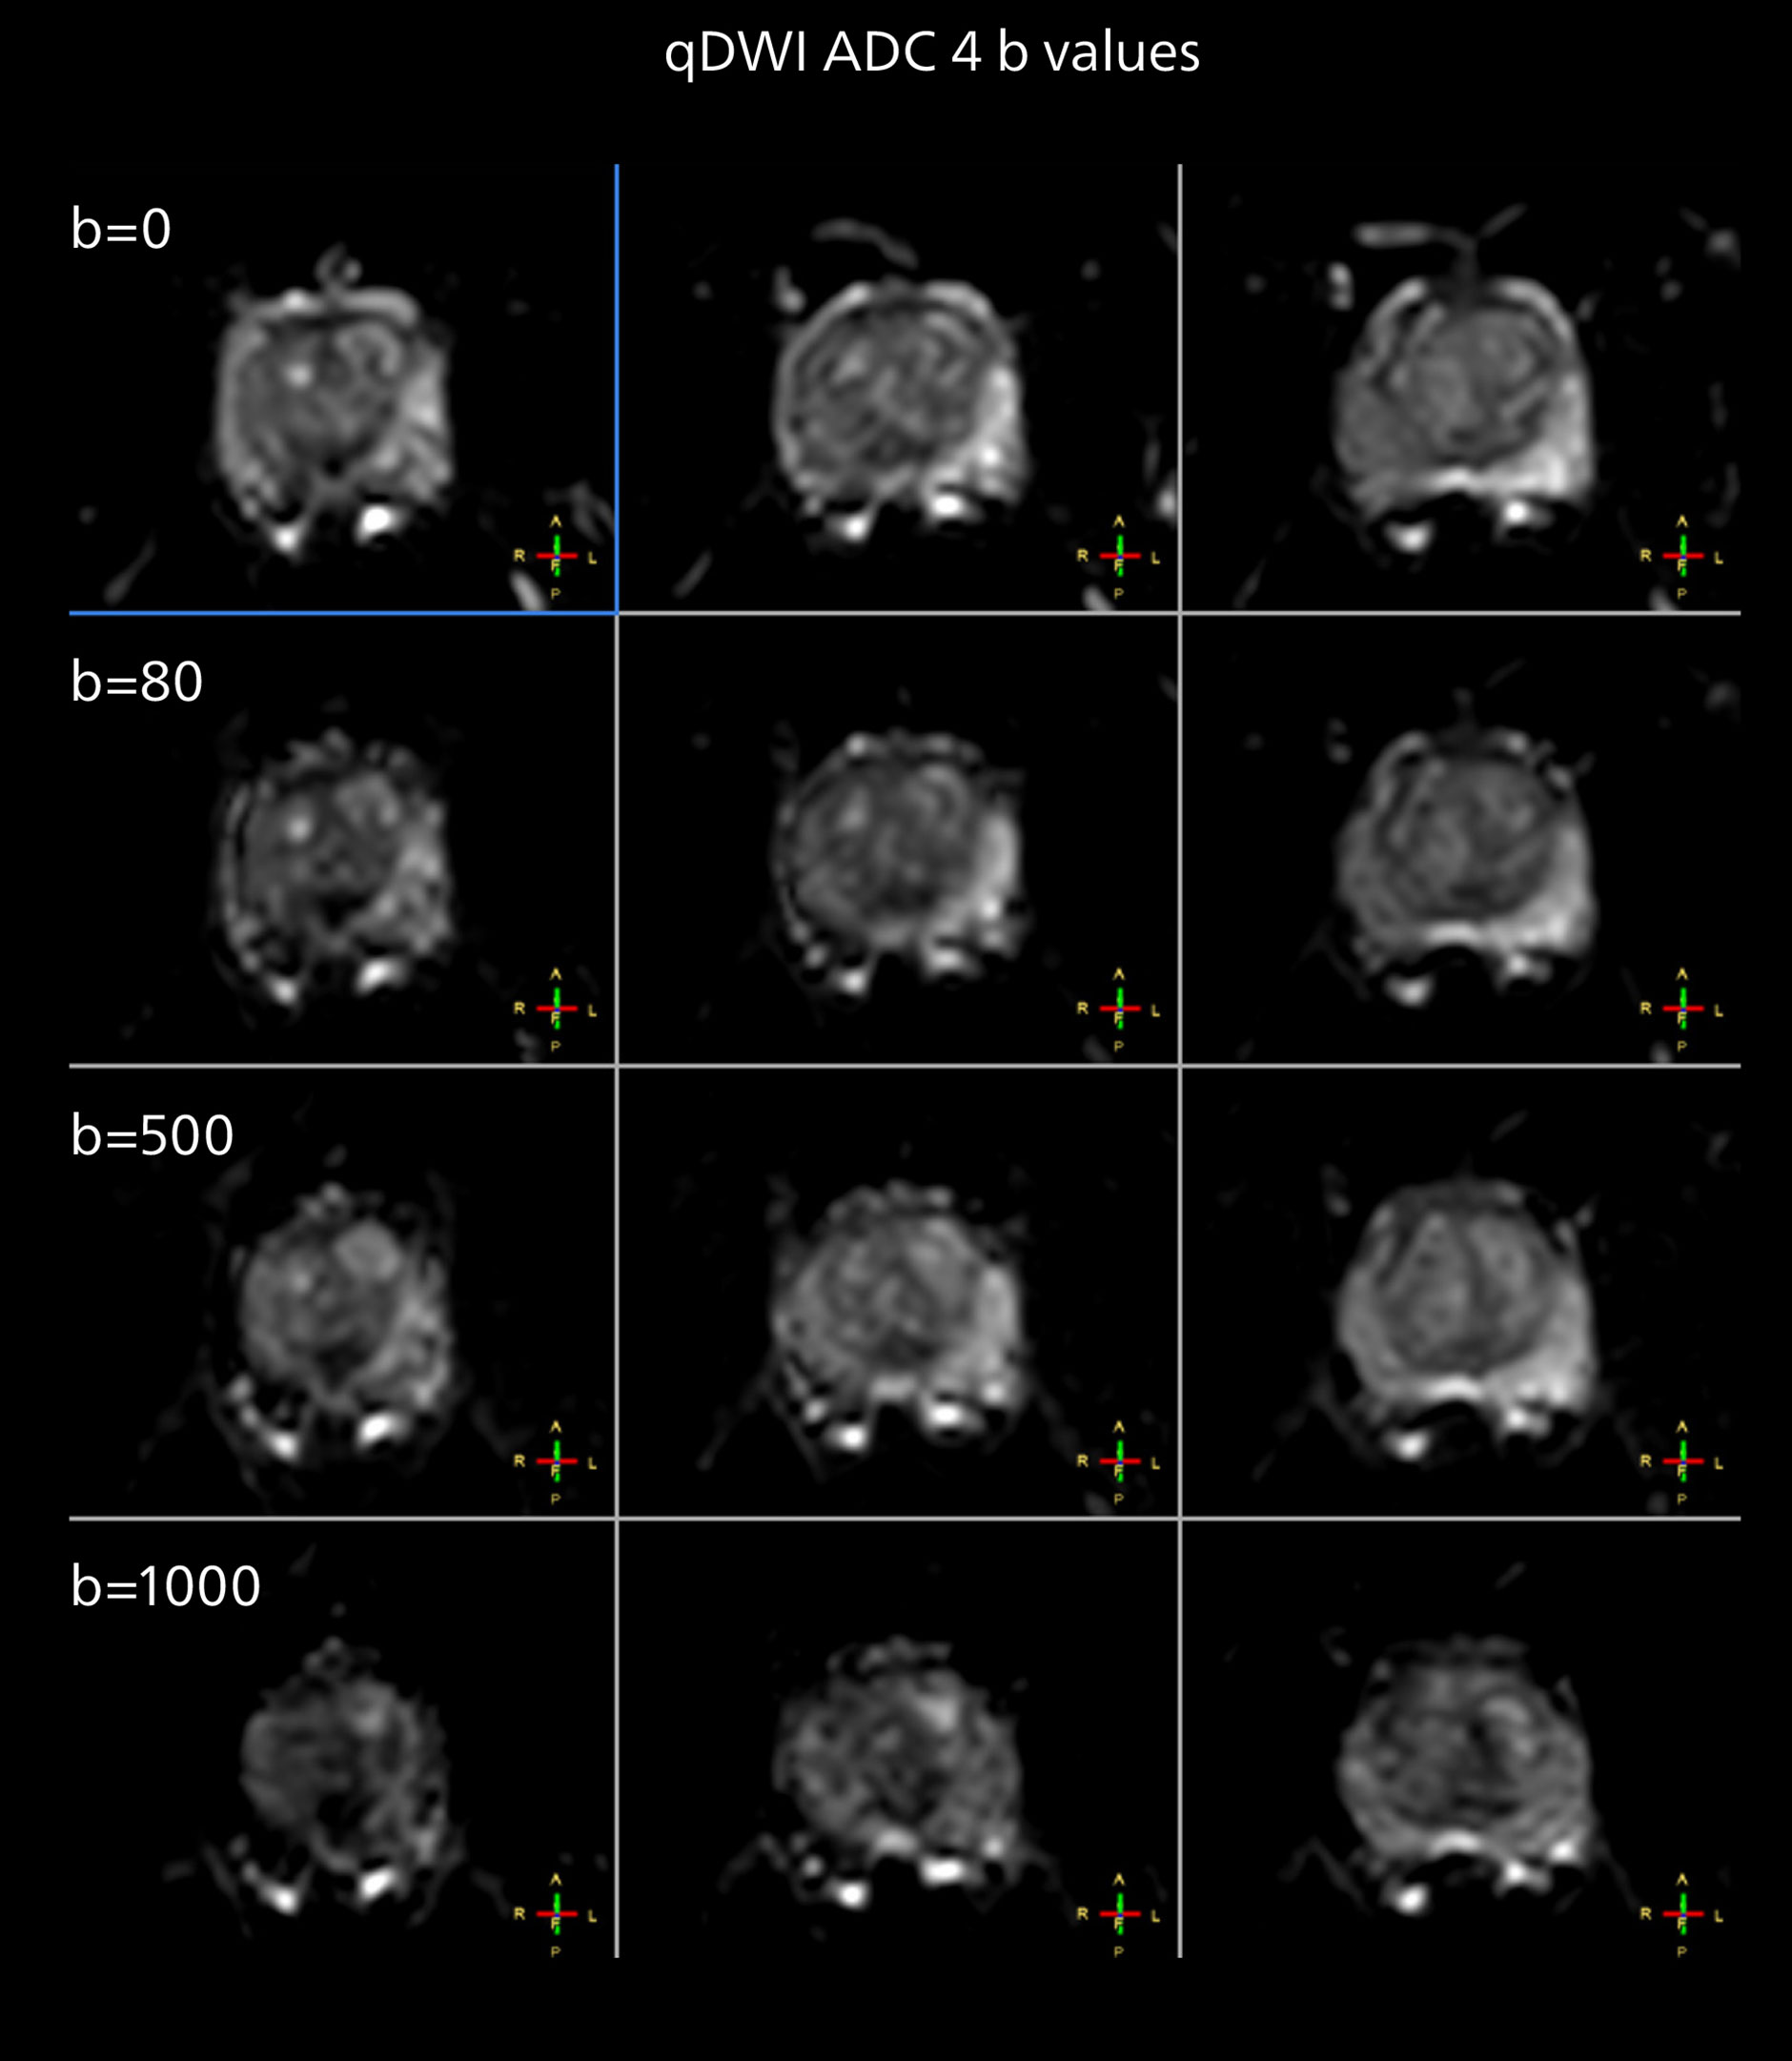

The examples on the left show the regular clinical diffusion protocol with four b-values up to b1000 s/mm². On the right, the T2W image shows a hypointense lesion that has low ADC and is clearly visible in b1400 and b2000 diffusion images, suggesting malignancy.

“From our experience, the diffusion imaging (DWI) seems to provide the most useful information in this process. And it is exactly the diffusion imaging that benefits much from the powerful MR 7700 gradients. So, we will investigate how even higher resolution DWI may enable an innovative approach in this area. The team also aims to investigate multiparametric imaging in combination with machine learning.”

The prostate DWI done so far with the MR 7700 looks promising; the quality of visualizing the gland and the areas of disease seems significantly improved. “In one of our first prostate patients we were already able to acquire a quite high-resolution diffusion image – using a b-value of 3000 – that clearly delineated the prostate lesion. That was a very nice example of what the MR 7700 gradients can achieve,” he says.